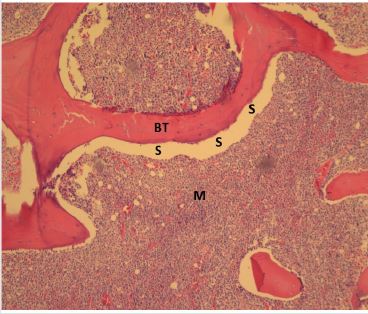

Unlike the conventional paraffin embedded biopsy sections which are thick (5-10 microns), these semi-thin sections of plastic embedded bone and bone marrow biopsies, when stained with Romanowsky stain, provide cellular morphology and structural details of the marrow in much greater detail than hitherto possible. Research conducted by the author [4-13] using the plastic embedding methods, resulted in the observation that unlike paraffin embedding (Figure 7), plastic embedded bone marrow biopsy sections the interface between the bone and marrow is well preserved (not separated) and remains intact. And as a result, the endosteal cells which line the bony trabeculae were clearly visible (Figure 8) and did not become deformed or displaced as they would have been under conventional formalin and paraffin processing. This clear picture is close to what would be observed in vivo and pointed out the significance of the endosteal region and the role of endosteal cells in the origin and the spread of leukemia [13].

Figure 7: A photomicrograph of hematoxylin and eosin stained paraffin embedded bone marrow biopsy section demonstrating complete separation/dissociation between bone and marrow. BT-bone trabecula, M- bone marrow, S- area showing complete separation/dissociation of bone and marrow.